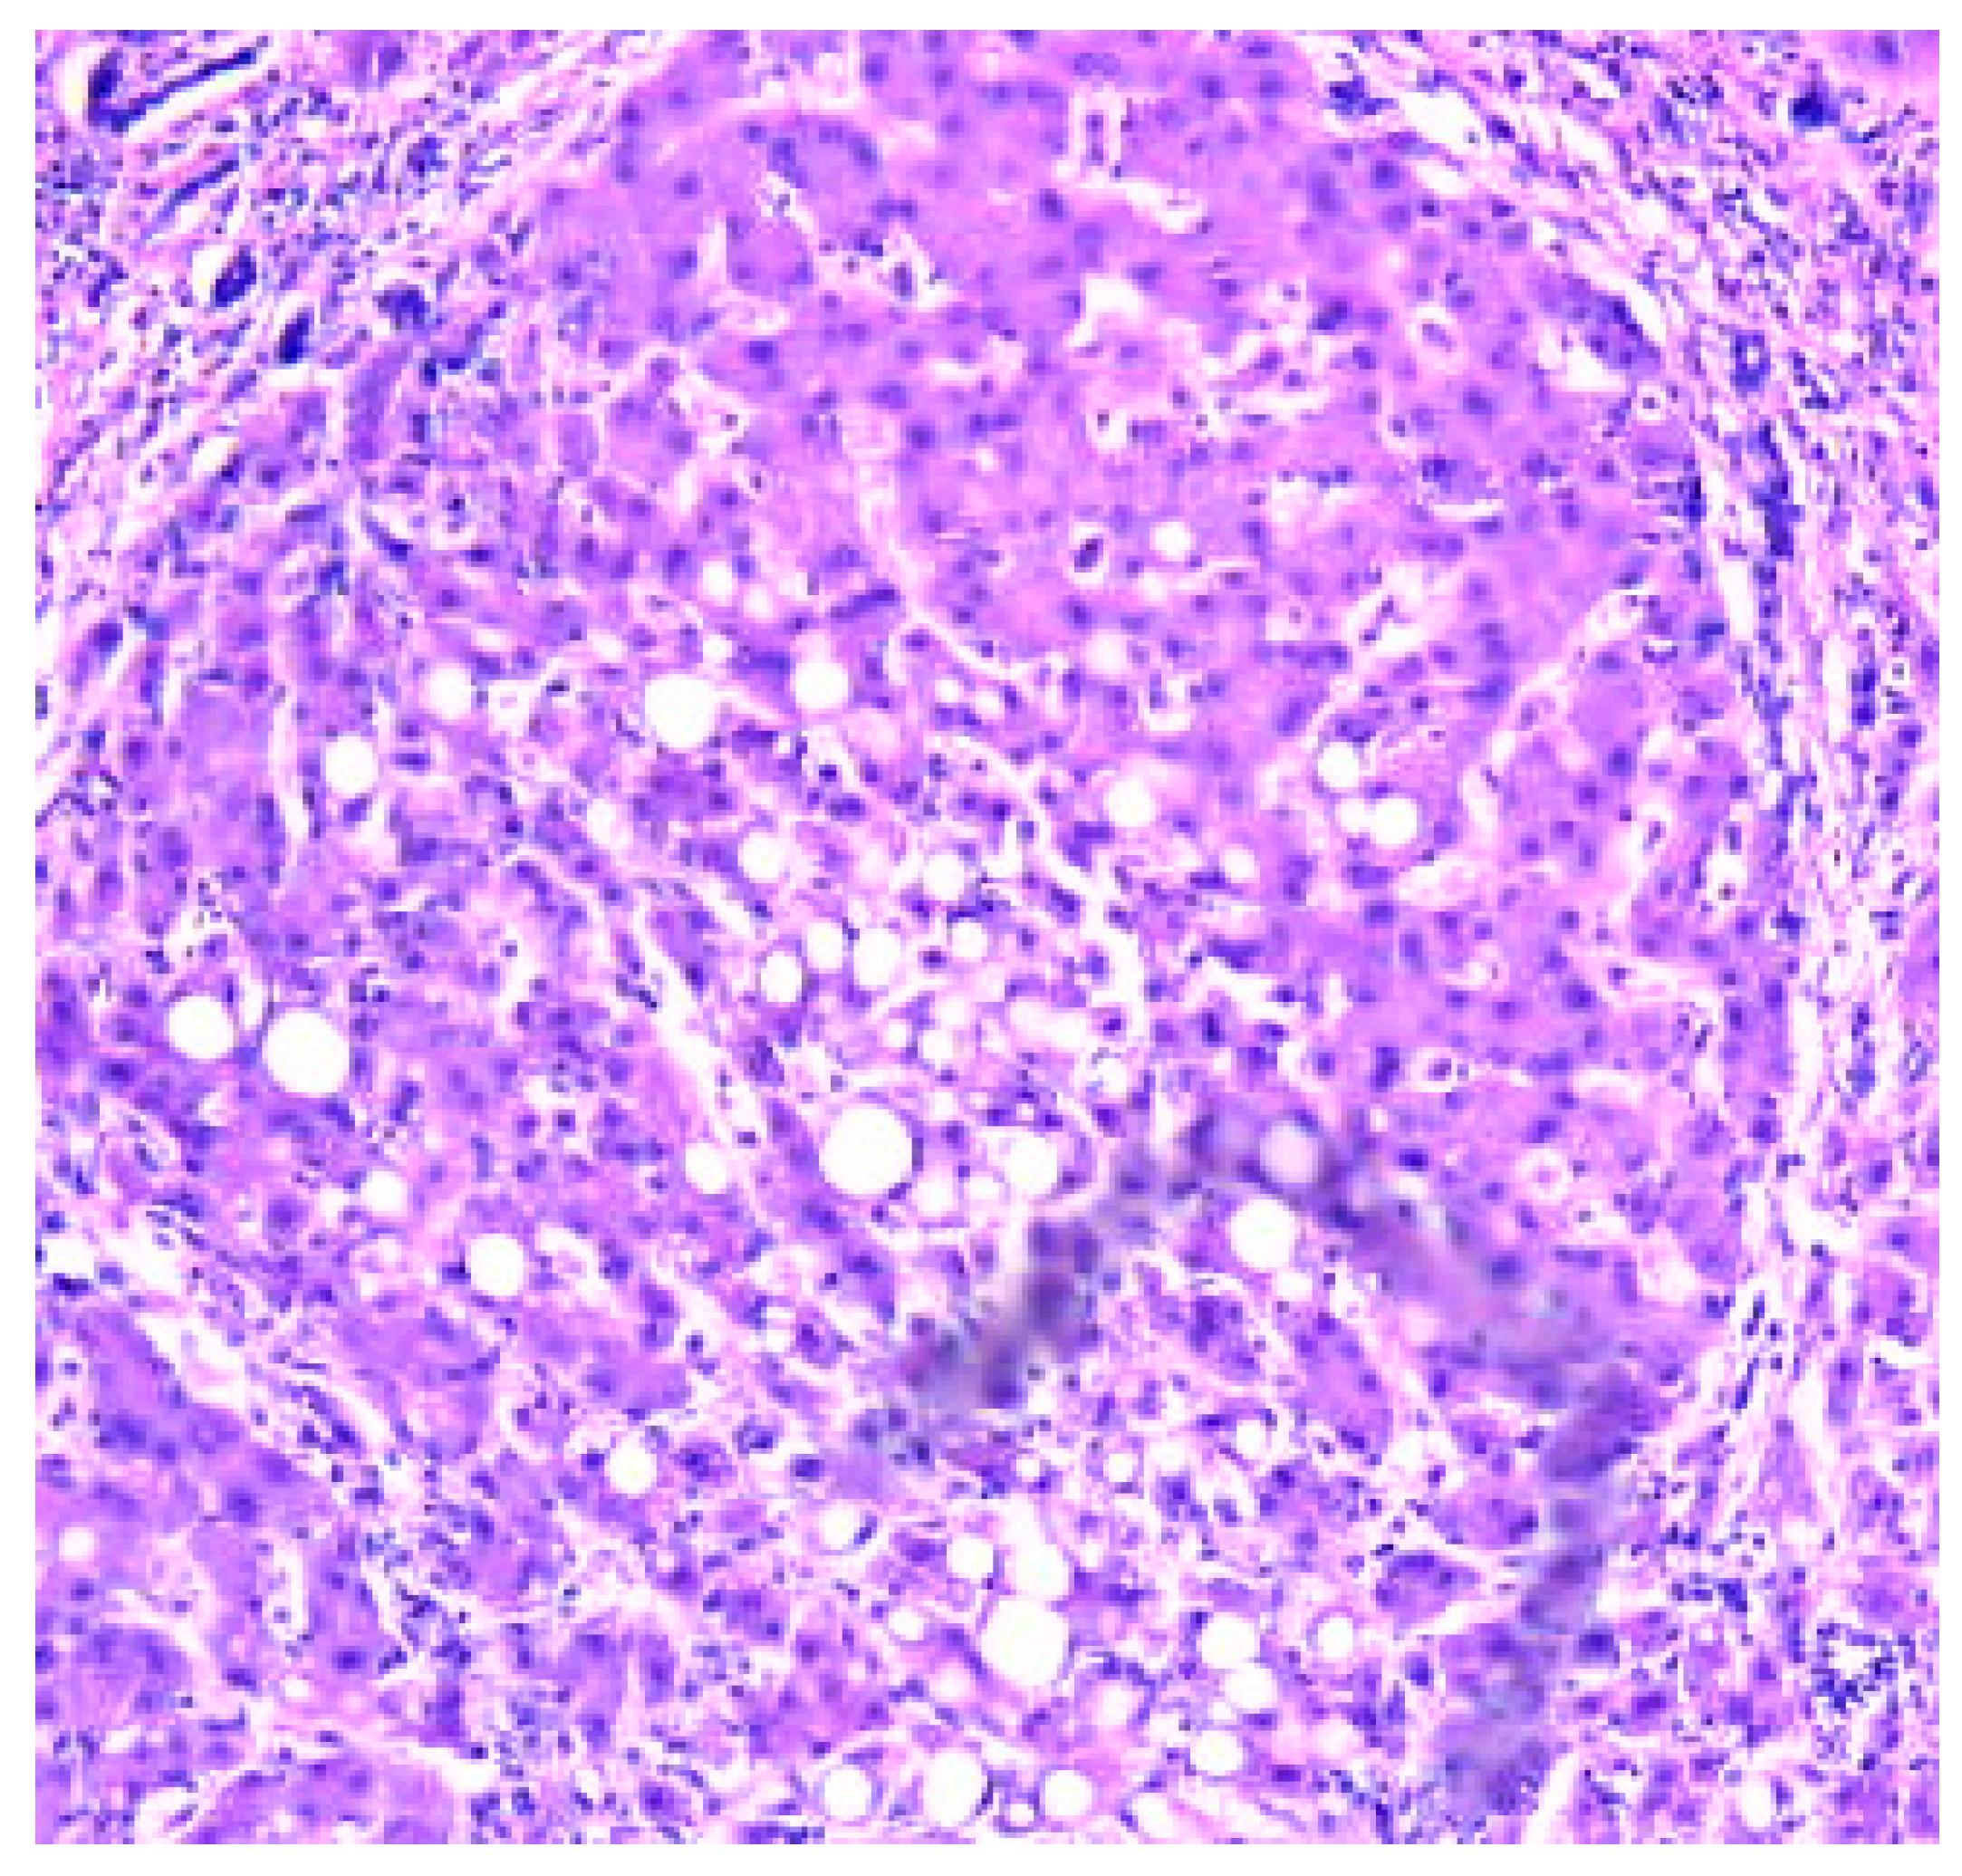

- Zone I is considered to be the periportal region of hepatocytes and are the best perfused and first to regenerate due to their proximity to oxygenated blood and nutrients. Implication in oxidative metabolisms.

- Zone II is defined as the pericentral region of the hepatocytes.

- Zone III has the lowest perfusion due to its distance from the portal triad. Implication role in detoxification.